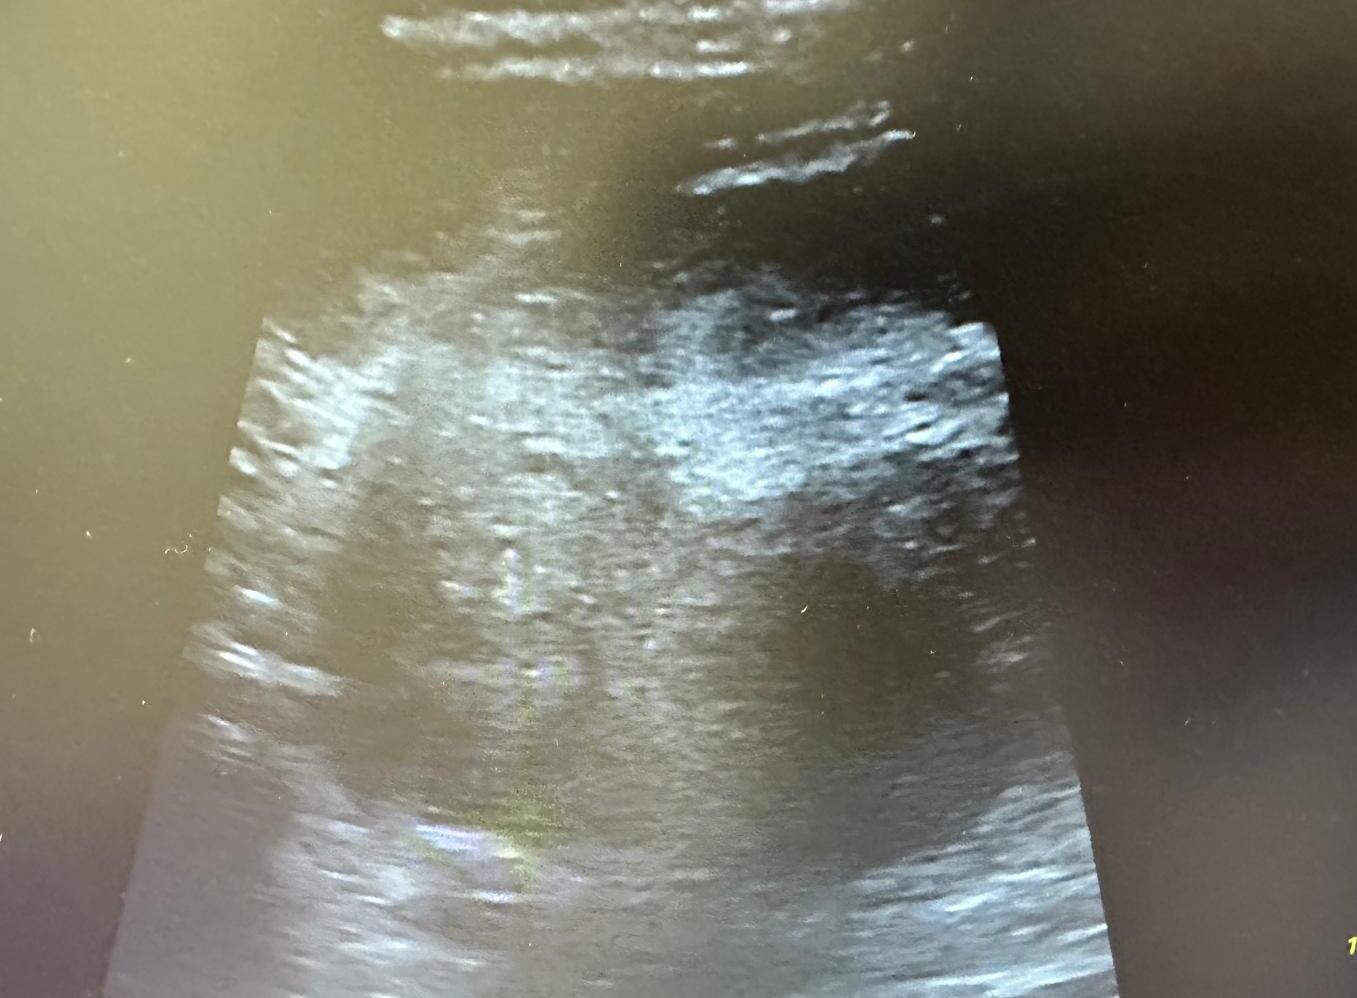

A nivel ecográfico se visualiza imagen profunda, heterogénea, de márgenes poco definidos, sin captación Doppler, más profunda que el margen del glúteo medio.